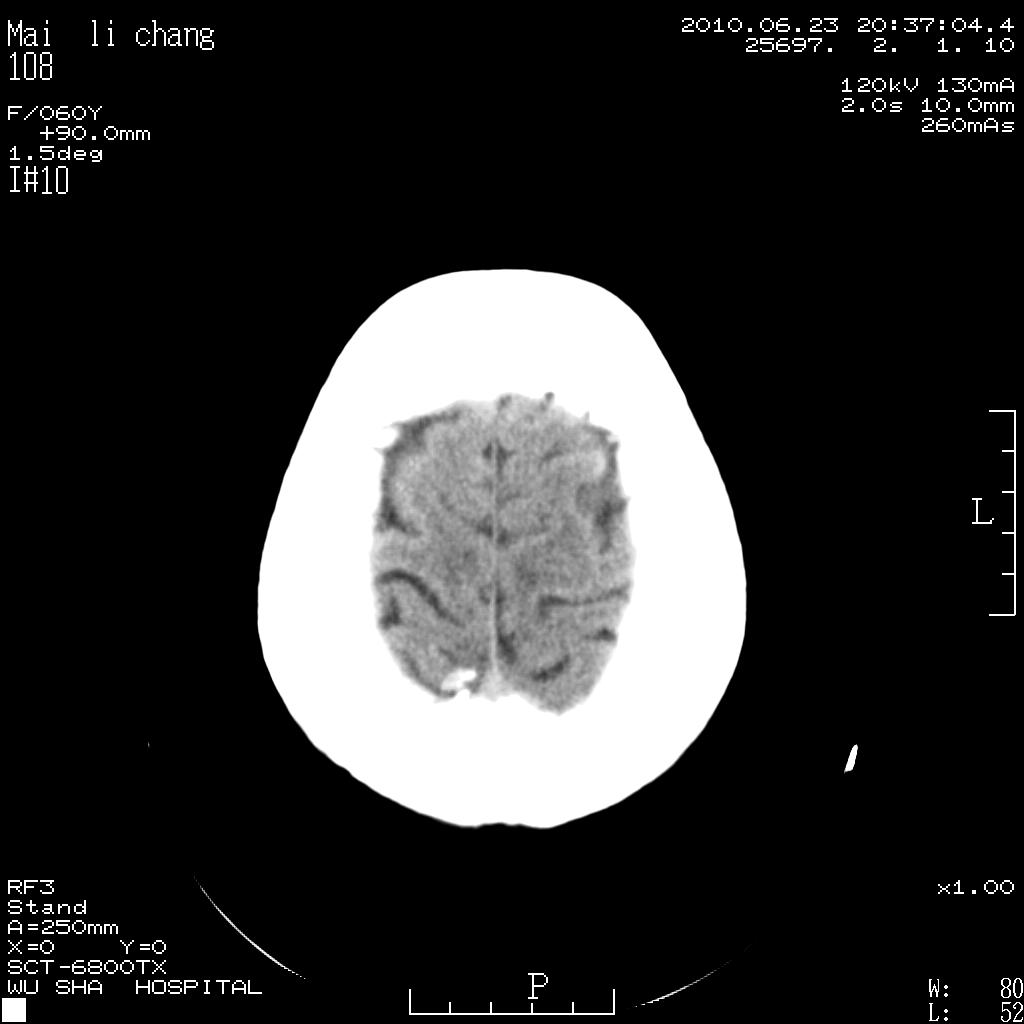

女性,60岁,右手无力一天

左侧基底节区及放射冠区多发脑梗塞。

左侧基底节区及侧脑室旁多发脑梗塞

左侧基底节及放射冠区脑梗塞。